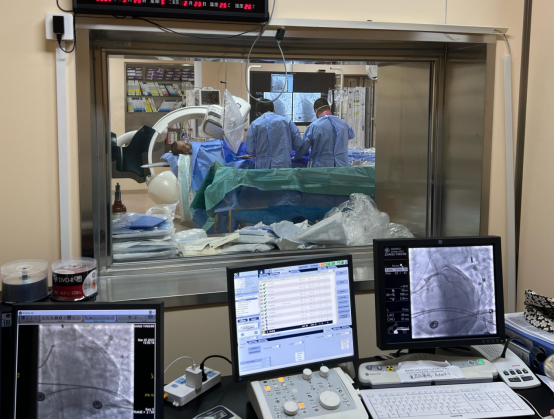

在从江北患者家中送往医院的路上,急救医生就将心电图发到哈医大一院胸痛中心微信群里,医生会诊后即启动导管室做好手术准备。到医院后,在无核酸结果的情况下,张先生直接被推进急诊负一层的负压导管室,而此时张先生已有心率减慢、血压下降状况。经紧急冠脉造影后发现,冠状动脉左主干尾部被一个大血栓阻塞,远端完全闭塞。在非常凶险情况下,医师立即为他植入IABP(主动脉内球囊反搏装置)以维持血压,并在IABP保护下行冠脉内血栓抽吸和支架植入术,几分钟后张先生的血管被开通,命总算被救了回来。患者入医院大门到导丝通过病变时间仅为30分钟,而从急救医生接触患者到导丝通过病变时间也仅为50余分钟。

到达医院后,刘先生在无核酸报告的情况下被推到负压导管室,紧急造影显示为左主干尾部90%狭窄,前降支近端90%狭窄并血栓影,回旋支完全闭塞。刘先生在IABP保护下成功进行了左主干血管开通,入医院大门到导丝通过病变时间仅为29分钟。

“左主干病变曾被认为是介入治疗的禁区,但随着技术和器械的发展,左主干病变急诊介入治疗已不再遥不可及。”孙延明介绍,哈医大一院胸痛中心介入团队每年完成超1000例急诊介入手术,医师技术先进、经验丰富,且有IABP、IVUS等仪器设备加持,挽救了大量患者生命。

两名左主干病变患者之所以能够成功救治,除了和家属送医及时以及过硬的医疗团队有关外,还和医院合理的救治流程密不可分。对于急性心梗来说,时间就是心肌,时间就是生命,在疫情防控常态下,来哈医大一院的急性心肌梗死患者,即使没有核酸报告亦可在负压导管室行急诊手术,无时间耽搁,这也为患者跑赢死神多了一份生命保障。